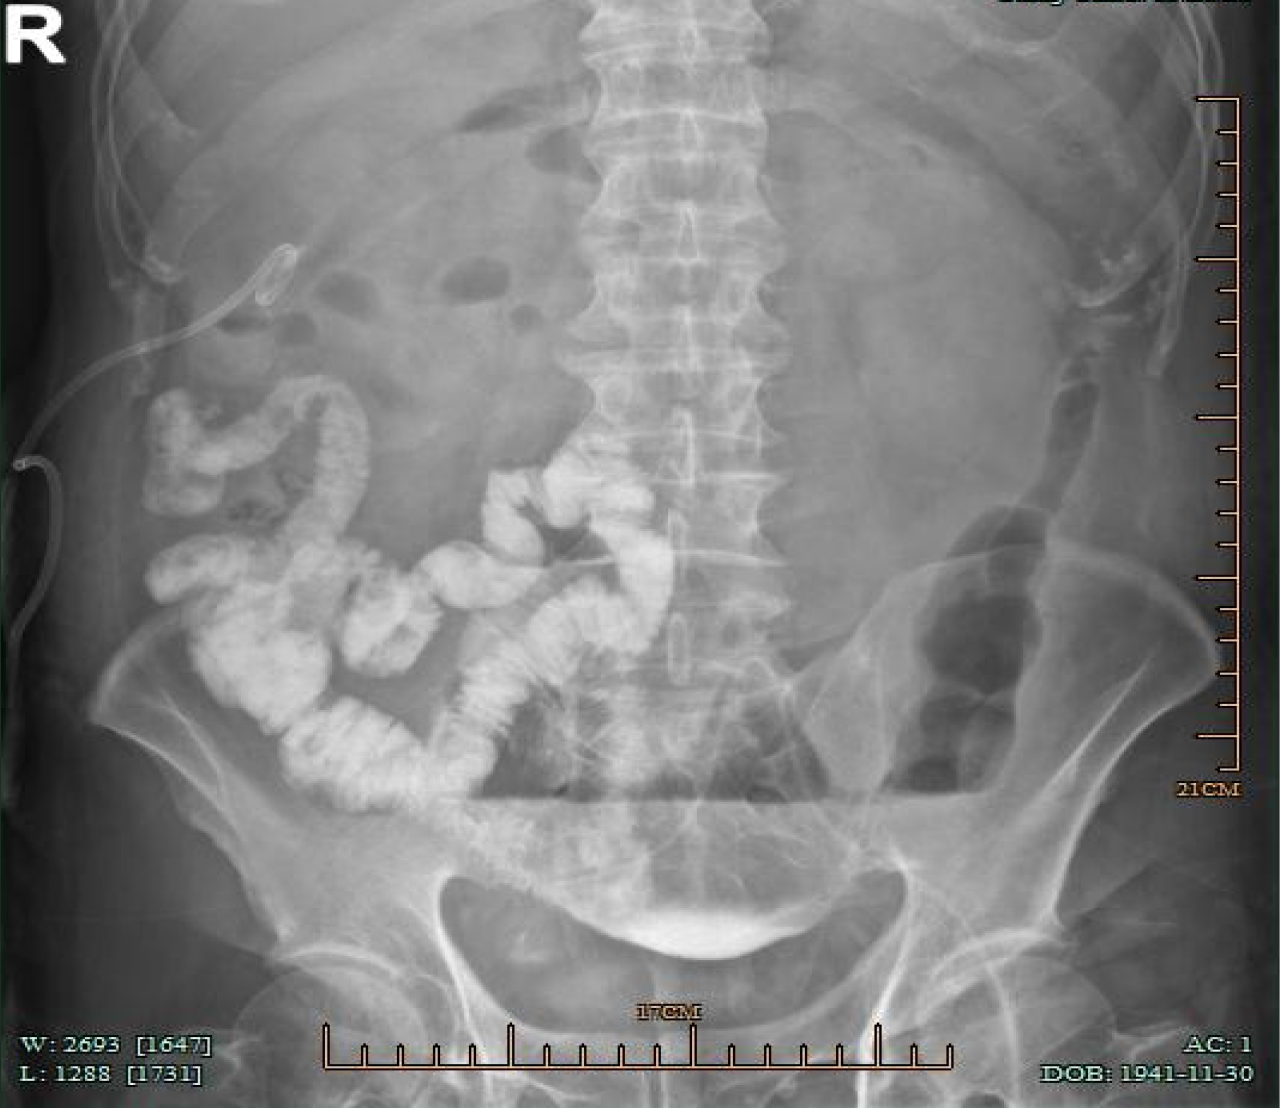

Figure 1

After injection of contrast agent through the original abdominal drainage tube in the left lower abdomen, the abdominal plain radiograph showed the small intestine in the right middle and lower abdomen filled with contrast agent.